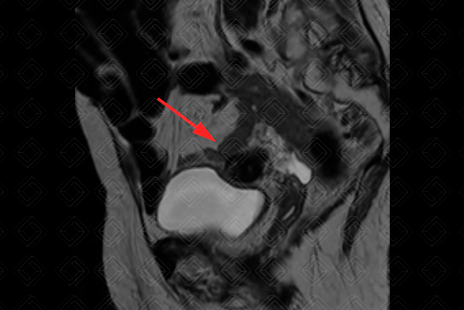

Descrição das figuras 5 e 6: Paciente do sexo feminino, 46 anos, com leiomiomas uterinos observados na sequência T2 sagital e axial, como formações arredondadas, com marcado baixo sinal, intramurais/subserosos (setas vermelhas).